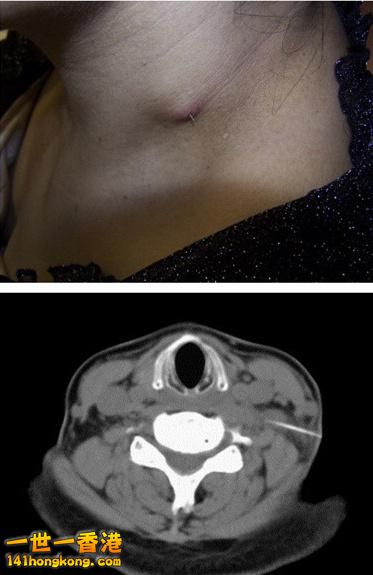

【案例三】:

刺穿腸壁的魚刺

2.jpg